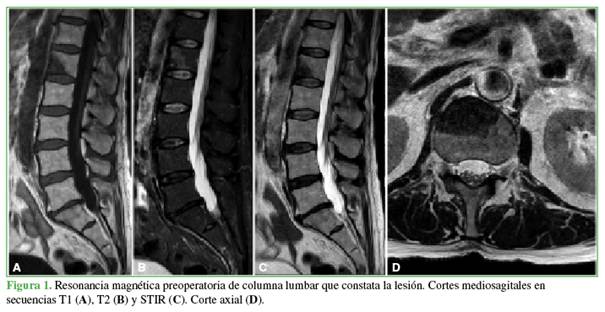

En la Figura 1, se muestran las imágenes de resonancia magnética de columna lumbar, con cortes sagitales, de las secuencias T1, T2 y STIR, así como un corte axial sobre el cuerpo vertebral de L1. Se observa una lesión que compromete la estructura del cuerpo vertebral e involucra la columna anterior en relación predominante con el segmento L1-L2, sin compromiso del canal vertebral, hipointensa en las secuencias T1/T2 e hiperintensa en la secuencia STIR.